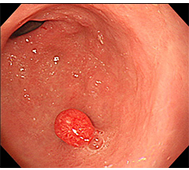

食道がん

- 内視鏡治療 :病変がリンパ節転移の無い早期食道がんに対し、内視鏡治療が行われます。